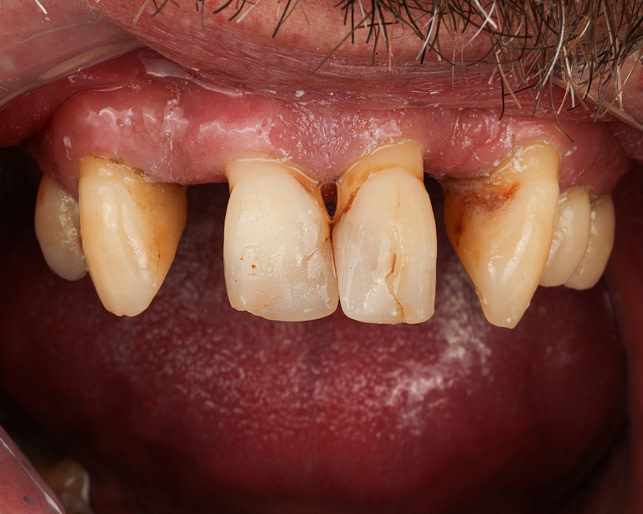

Before

After